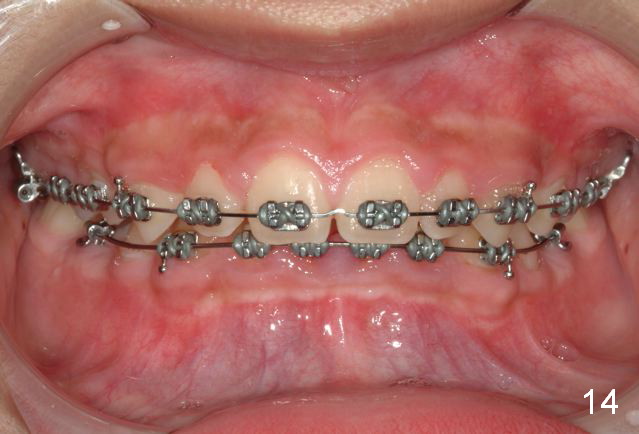

Brackets were placed on 2015_09_06 (Fig.11-13, Phase I pre-orthopedic tooth movement, leveling in advance of Herbst appliance therapy using ankylosed Es).   Six months later (Fig.14-16), LR7 did better, LL7 did not and will need intervention. But intrusion of L 3-3 looks good.

Now back to orthodontics, I did not want to place bands on the lower 6s initially because I thought that would block the ectopic 7s for sure and seal their fate.

The effect would be quite similar had I banded the 6s but we know they can move, the Es cannot.

I will have the LL8 extracted and the adjacent 7 elevated and/or place an interdental brass wire. I will have it up righted in no time and not plan to slenderize the E.